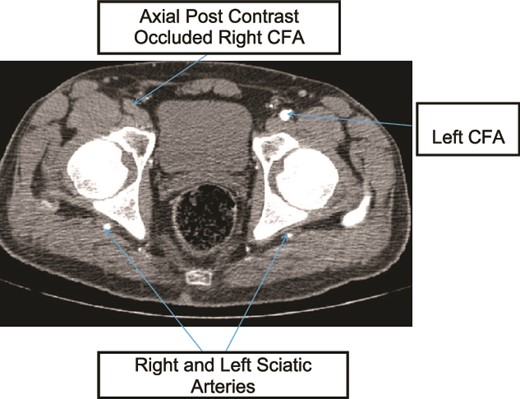

A 45-year old known diabetic and hypertensive male patient presented with right foot pain of one year. He had right calf claudication for 4 years and associated darkening of the right little toe of 1 month. He was a cigarette smoker for 15 years, but had discontinued 1 month prior. On examination, he had right fifth digit dry gangrene with non-palpable pulses in the right popliteal artery (PA), dorsalis pedis artery (DPA), or posterior tibilias artery (PTA). Preoperative ABI was not recordable (no flow detected in DPA or PTA with handheld Doppler ultrasound). Doppler ultrasound showed ~90% occlusion of right common femoral artery (CFA) with hemodynamically significant downstream insufficiency and scattered foci of arterial wall calcification and wall thickening of bilateral LL arteries. CTA showed mild atherosclerotic disease, long segment right CFA, superficial femoral artery (SFA), proximal profunda femoris (PF), proximal and mid right PA occlusion and right PSA supplying collateral to the distal PA with right tibio-peroneal trunk atherosclerotic occlusion (Figs 1–3). Patient underwent right CFA thrombectomy and femoro-popliteal (supragenicular) bypass using ipsilateral subcutaneously tunneled reversed great saphenous vein (GSV). Postoperative ABI was 1.2 and he was discharged on Per Os (PO) anticoagulant (Rivaroxaban). On a 3-year postop follow up, patient had mild claudication with no rest pain or wounds.

Case 1—axial image of LL CTA of the bilateral LL arteries at the level of the femoral head showing occlusion of the right CFA and bilateral PSA with larger caliber right PSA.